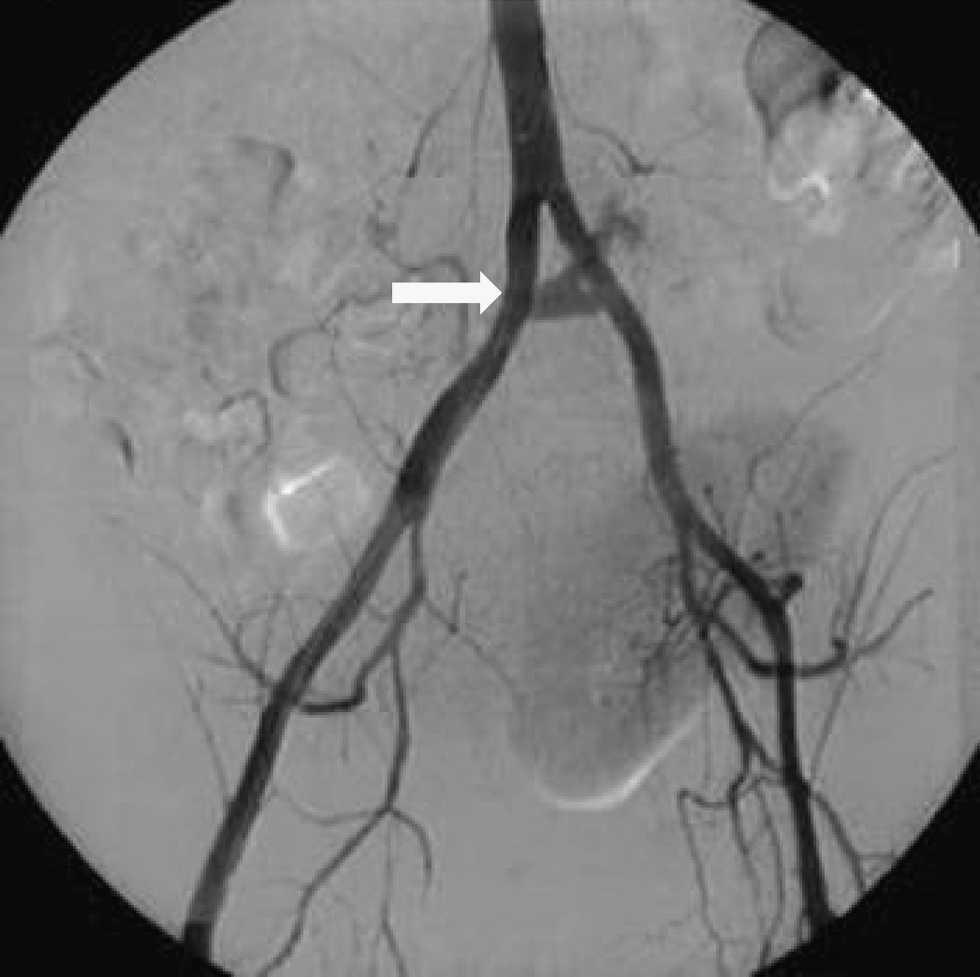

Dado que el paciente se encontraba en estado de shock hemodinámico, se decidió la intervención quirúrgica urgente. Se observó una pancreatitis aguda necrótica del injerto y distensión del duodeno y el yeyuno del receptor con sangre en su interior. Además se palpó una masa pulsátil en la anastomosis vascular arterial entre la esplénica y la mesentérica. Ante estos hallazgos, se practicó una arteriografía intraoperatoria que puso de manifiesto un seudoaneurisma de la anastomosis arterial esplenomesentérica del injerto, con extravasación de contraste hacia el duodeno del injerto (figura 2). Se embolizó mediante la inserción de coils a nivel de la arteria mesentérica del injerto. Una vez estabilizado el paciente se realizó la exéresis del injerto en bloque y la reconstrucción intestinal.

Figura 2. La arteriografía pone de manifiesto la extravasación de contraste a nivel de la arteria ilíaca y la presencia de un seudoaneurisma.